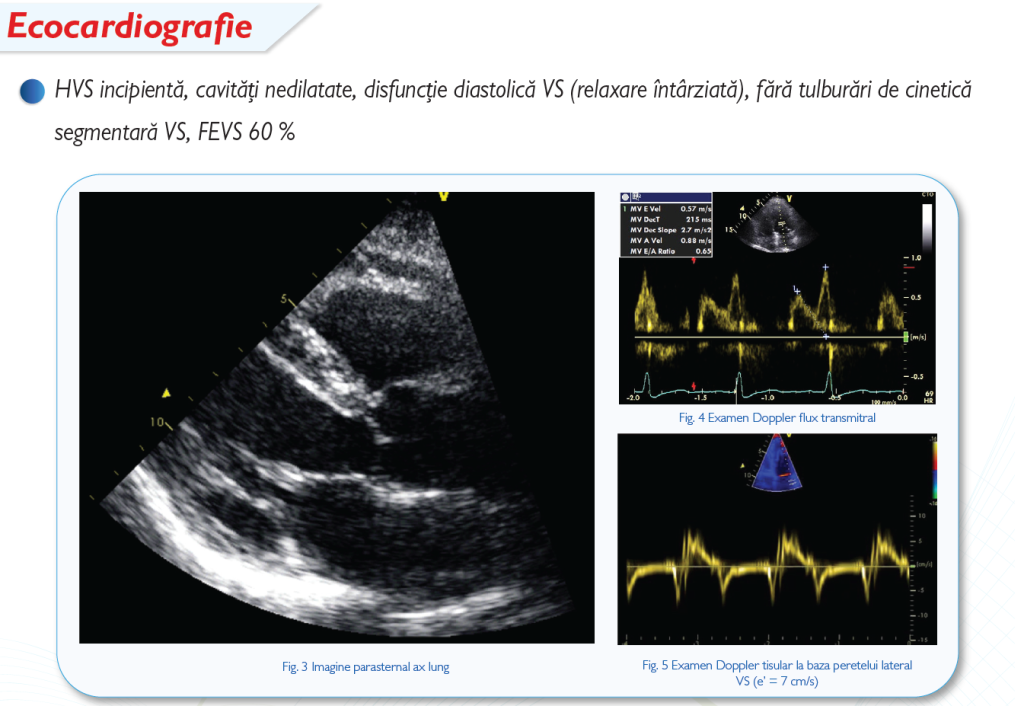

Pentru a accesa orice fel de conţinut, , sau înregistraţi-vă în mai puţin de 3 minute